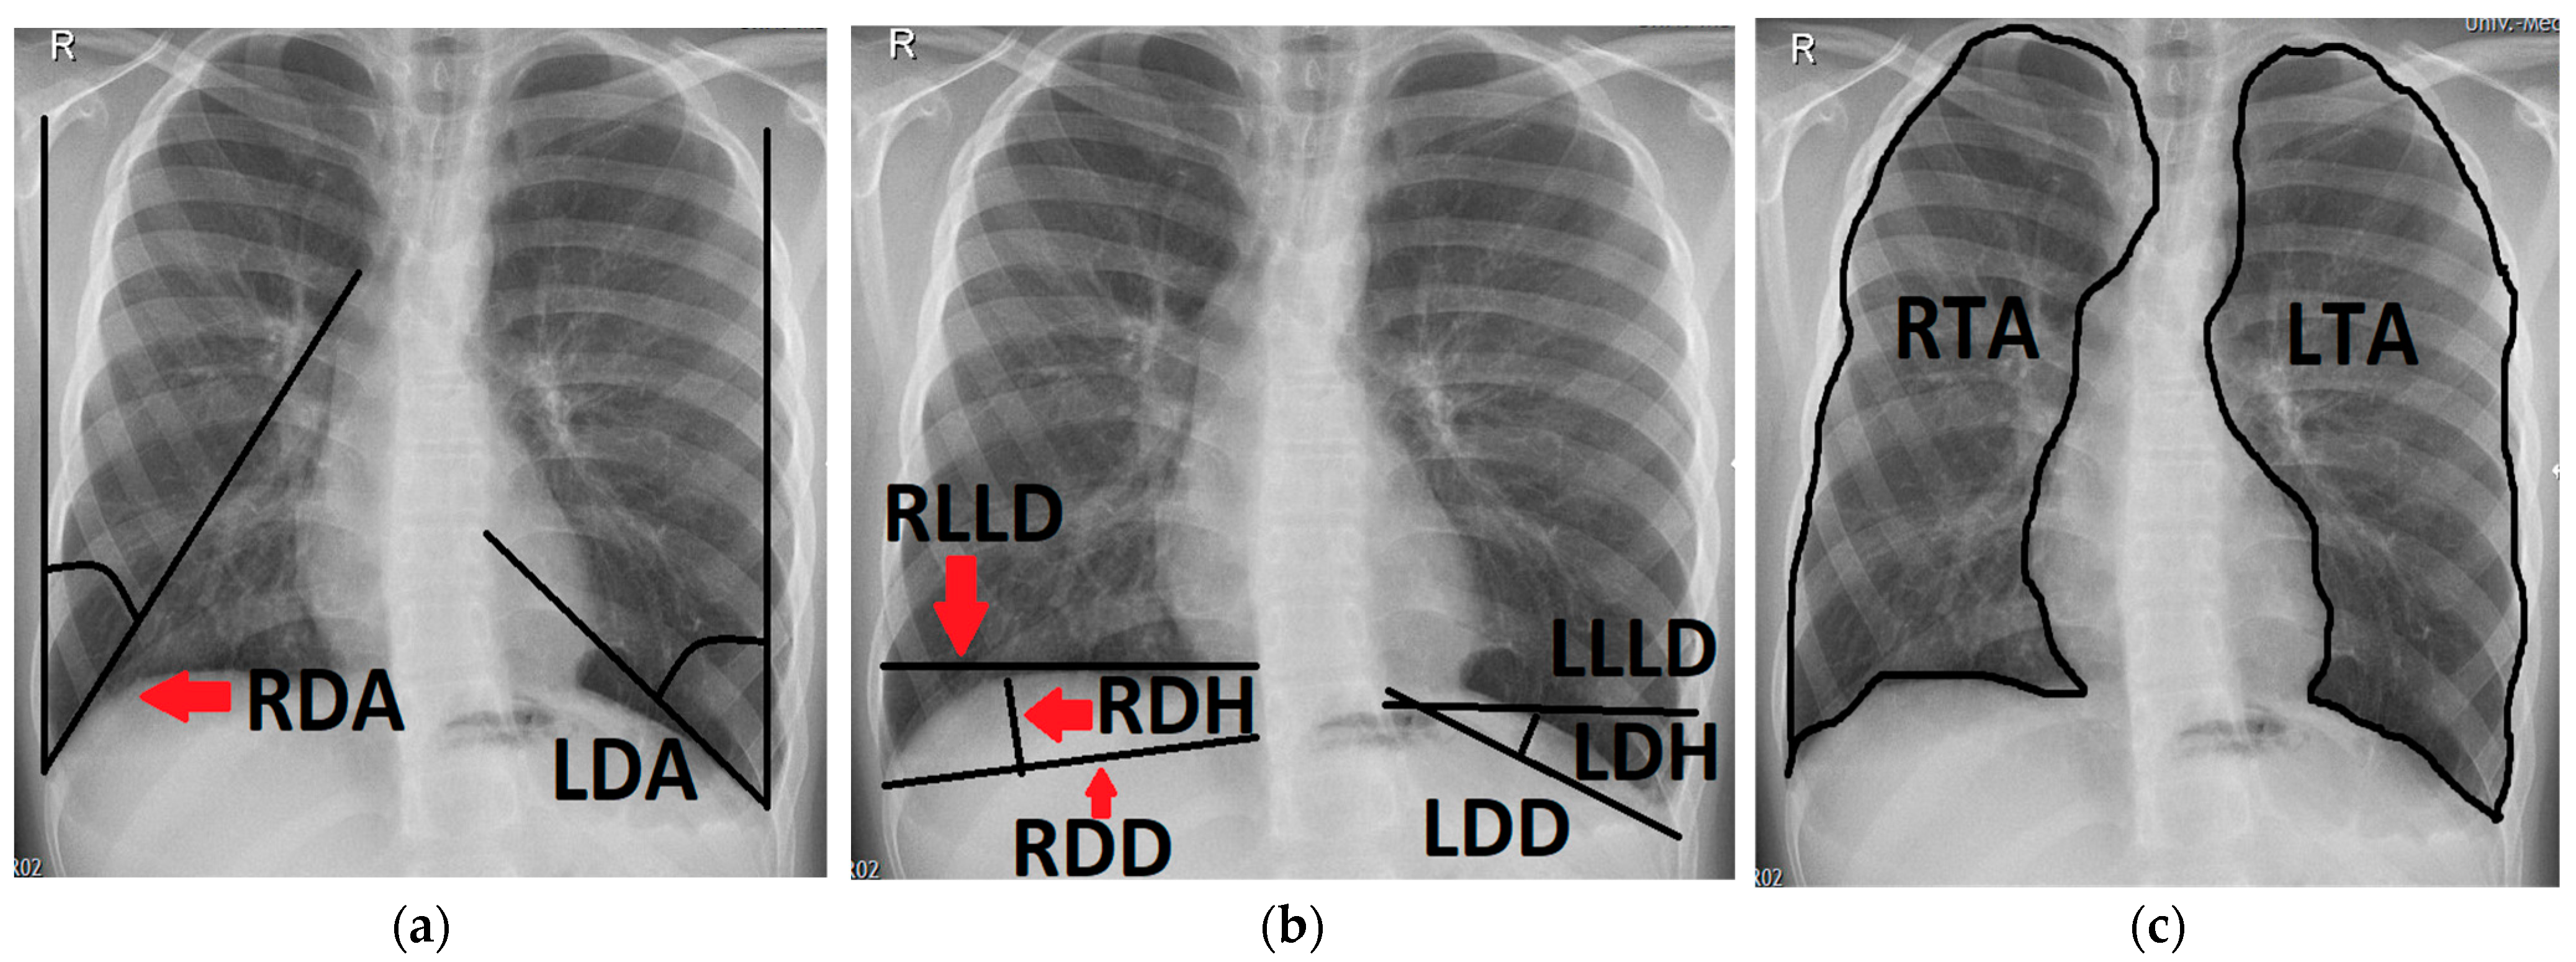

Figure 1.

Chest radiograph of a 6-month-old patient after left-sided CDH repair with a cone-shaped patch in the neonatal period; measurements of the following variables are outlined (black line) and labeled on the patient’s right side (red arrows): (a) right and left diaphragmatic angle (RDA, LDA); (b) right and left diaphragmatic diameter (RDD, LDD), right and left diaphragmatic height (RDH, LDH) and right and left lower lung diameter (RLLD, LLLD); (c) right and left thoracic area (RTA, LTA).

- The left and right diaphragmatic angle (LDA, RDA), which were defined by the angle between the lateral chest wall and the tangent to the convex side of the ipsilateral diaphragm coming from the costodiaphragmatic recessus.

- The left and right diaphragmatic diameter (LDD, RDD), measuring from the costodiaphragmatic recessus to the medial limit of the diaphragm.

- The left and right diaphragmatic height (LDH, RDH), measured as the perpendicular line from the diaphragmatic diameter to the apex of the diaphragm.

- The left and right lower lung diameter (LLLD, RLLD), measuring the width of the lung from its limit at the lateral chest wall to its medial limit at the level of the apex of the diaphragm.

- The left and right thoracic area (LTA, RTA) were defined by delineating the outer border of the lung tissue, excluding the mediastinum and the cardiac shadow.

- The left and right diaphragmatic curvature index (LDCI, RDCI) were calculated via the quotient of the diaphragmatic diameter and the diaphragmatic height (e.g., LDD/LDH = LDCI). A large LDCI therefore indicates a flat diaphragm with only a small curvature.